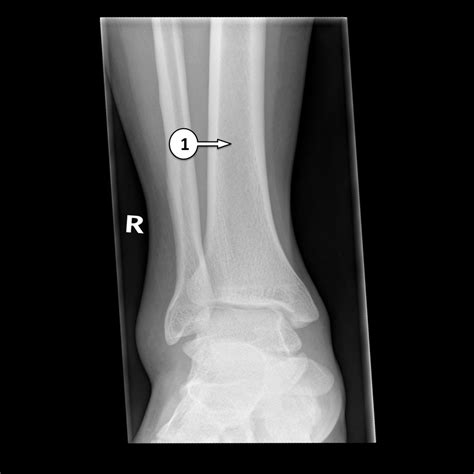

Interpreting a Normal Ankle Xray

Interpreting a Normal Ankle Xray involves examining the images for any abnormalities. Key areas of focus include:

• Bone density and structure

• Joint spaces and alignment

• Presence of fractures or dislocations

• Soft tissue swelling or inflammation

Radiologists look for signs of fractures, such as breaks in the bone continuity, and assess the overall health of the ankle joint. Any deviations from the normal anatomy are noted and reported.

Common Findings in a Normal Ankle Xray

A Normal Ankle Xray typically shows the following structures clearly:

• Tibia and fibula (the two bones of the lower leg)

• Talus (the bone that forms the ankle joint)

• Calcaneus (the heel bone)

• Joint spaces and cartilage

In a normal X-ray, the bones should appear smooth and continuous, with no signs of fractures or dislocations. The joint spaces should be uniform, and there should be no evidence of bone spurs or other abnormalities.